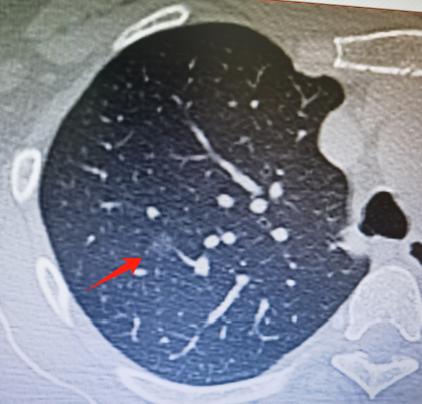

肺结节术后是“微浸润癌”的案例。这位患者52岁,平时生活习惯挺好,也不抽烟,没什么明显的高危因素。可最近体检时,发现肺上有个结节。从影像形态来看,我告诉他,要考虑“原位癌或者微浸润癌”的可能。 他一听到“浸润”两个字,就有点紧张,赶紧问我:“是不是有浸润成分就代表很危险?” 其实,原位癌可以理解为肿瘤细胞还“待在自己家里”,没有向外侵犯的能力,不会扩散也不会转移,所以它本身是安全的,不会致命。 而浸润癌,指的是癌细胞具备了向外侵犯的能力,有可能突破基底膜,向周围组织甚至更远的地方扩散。不过,只要发现得早、分期早,治疗效果通常也很好。 那么微浸润癌又是什么?它其实是一种非常早期的浸润状态,指的是肿瘤中只有极少一部分发生了浸润,而且这个浸润的范围小于5毫米。换句话说,它大部分还是原位癌的成分,只有那么一小点儿开始“往外走”。 正因为浸润的部分非常有限,微浸润癌的转移风险很低,恶性程度也很低,对人的生命基本上构不成大的威胁。 可以说,微浸润癌属于治疗效果和预后都非常好的一种类型。大量临床研究已经证实,无论是原位癌还是微浸润癌,做完手术后的治愈率都能达到99%以上——几乎可以理解为,这是一个“基本上能治好”的癌。 所以,大家不必一看到“微浸润”里有“浸润”两个字就过度紧张。关键在于早发现、早处理,这类早期癌是完全可控的。[作揖][玫瑰]胸外科乔贵宾医生肺结节[超话]